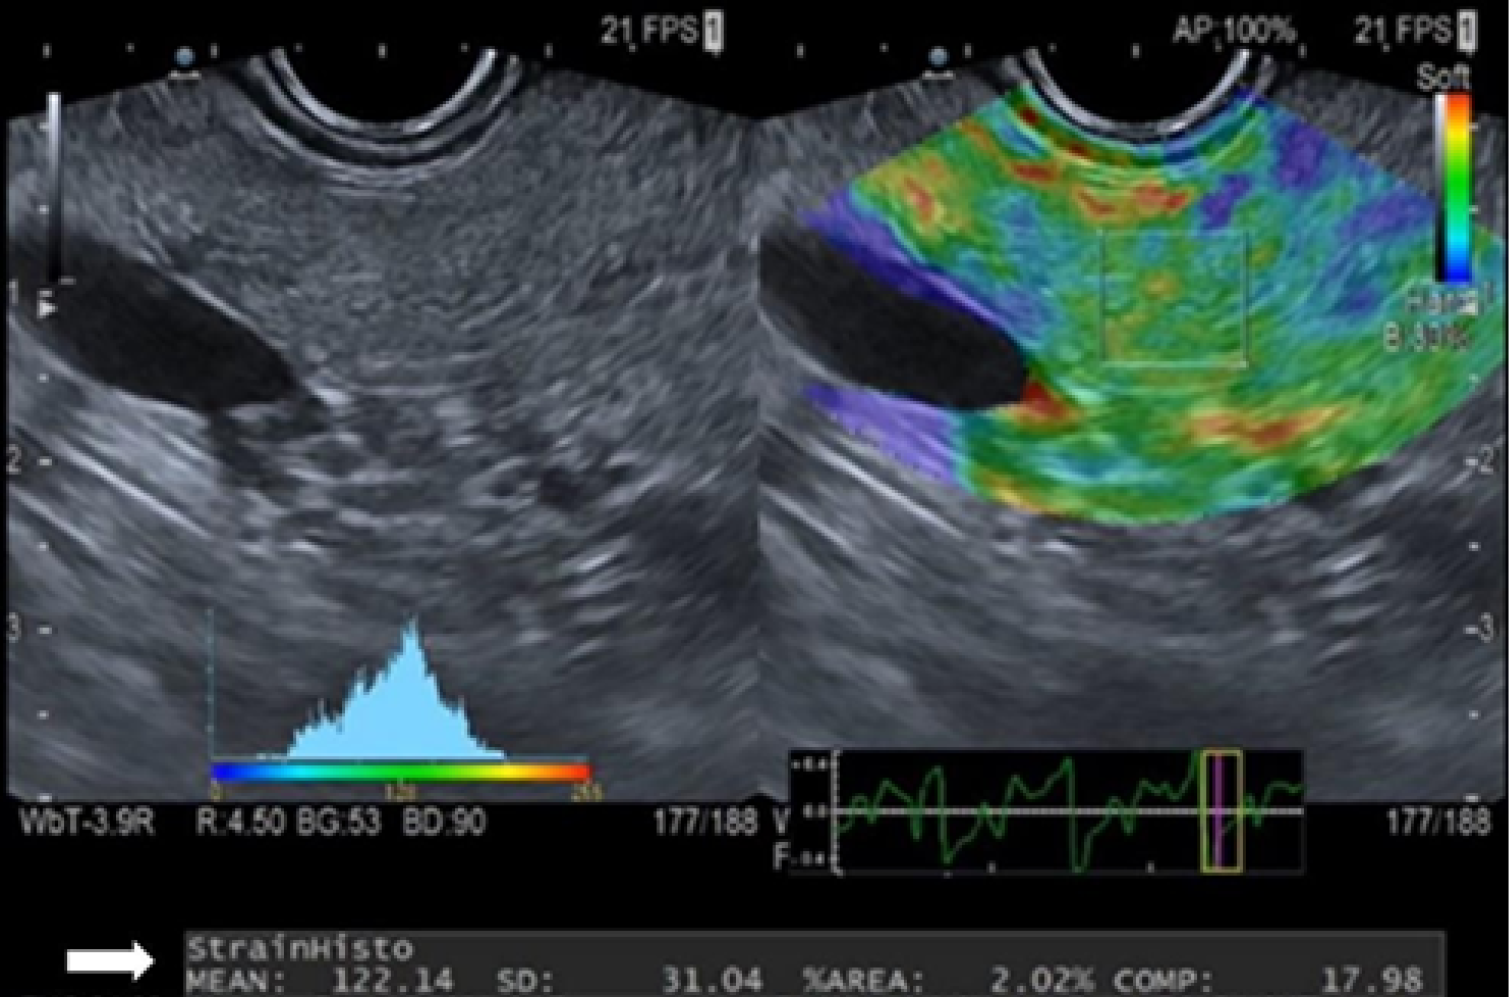

SH analysis was performed after verifying the absence of the aforementioned exclusion criteria. The probe was positioned against the gastric or duodenal wall, applying appropriate pressure to optimize the B-mode image. A frequency of 7.5 MHz was used for the B-mode probe. Measurements were taken exclusively from the pancreatic parenchyma, carefully avoiding the main pancreatic duct and major vascular structures. Elastography and B-mode images were displayed simultaneously in a split-screen format (Figure 1).

The elastography evaluation included a qualitative analysis to detect minor structural deformations (speckle motion) caused by compression within the B-mode image, where the degree of deformation reflects tissue stiffness. Tissue elasticity (on a scale of 0-255) was color-coded and overlaid on the real-time B-mode image. Blue, green/yellow, and red represented hard, intermediate, and soft tissues, respectively. Notably, this scale indicates relative rather than absolute tissue stiffness.

To obtain the SH value, a 1 cm2 square ROI was placed on the pancreatic parenchyma using the qualitative color scale and B-mode image for guidance. Integrated software then automatically generated a histogram, with the X-axis representing tissue elasticity from 0 (hardest) to 255 (softest) and the Y-axis representing the pixel count for each elasticity level within the ROI. The SH value was defined as the mean of all elasticity values within the selected ROI (Figure 1).